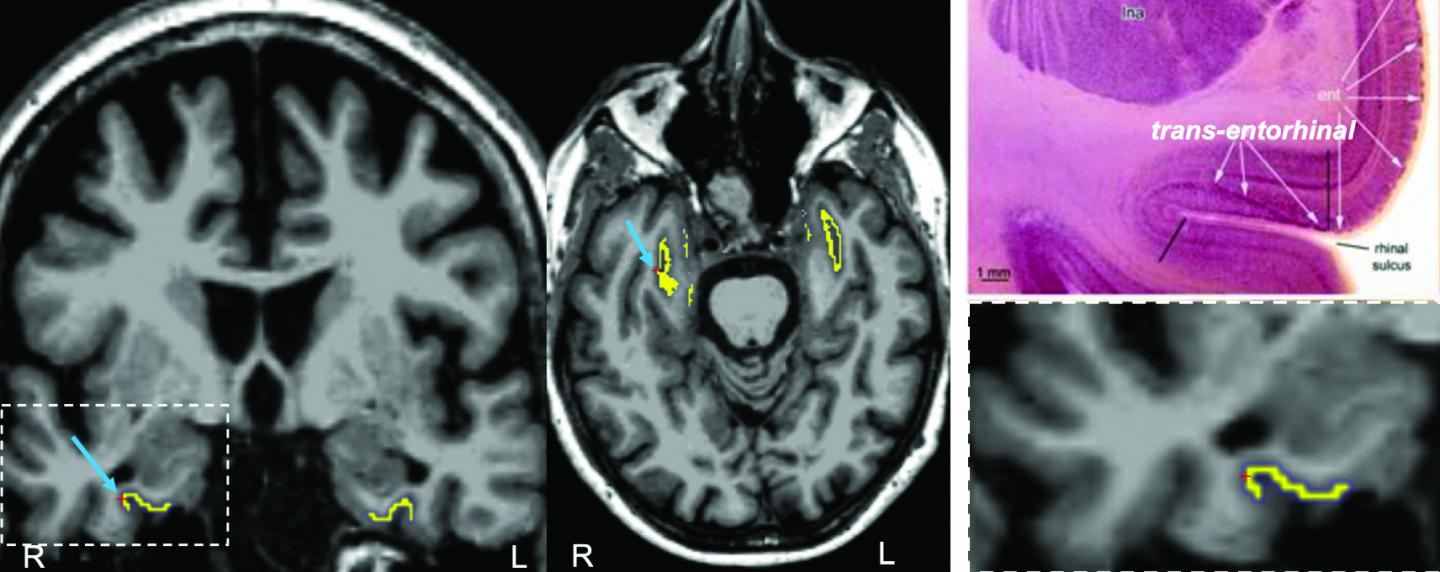

The researchers investigated TAU protein with PET imaging in the rhinal cortex (yellow) in the brains of patients. This material relates to a paper that appeared in the Jan. 20, 2021, issue of <i>Science Translational Medicine</i>, published by AAAS. The paper, by J.S. Sanchez at Massachusetts General Hospital in Boston, MA; and colleagues was titled, "The cortical origin and initial spread of medial temporal tauopathy in Alzheimer's disease assessed with positron emission tomography."

[Credit: J.S. Sanchez <i>et al., Science Translational Medicine</i> (2021)]